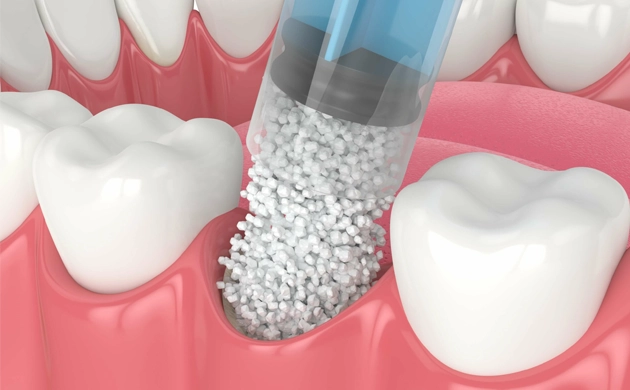

- Bone Graft

- Socket Preservation